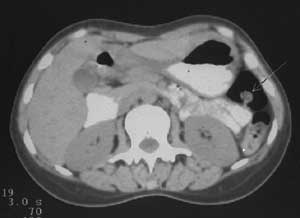

Рис. 7. Полип на ножке (стрелка) визуализируется на фоне газа в селезеночном изгибе толстой кишки.